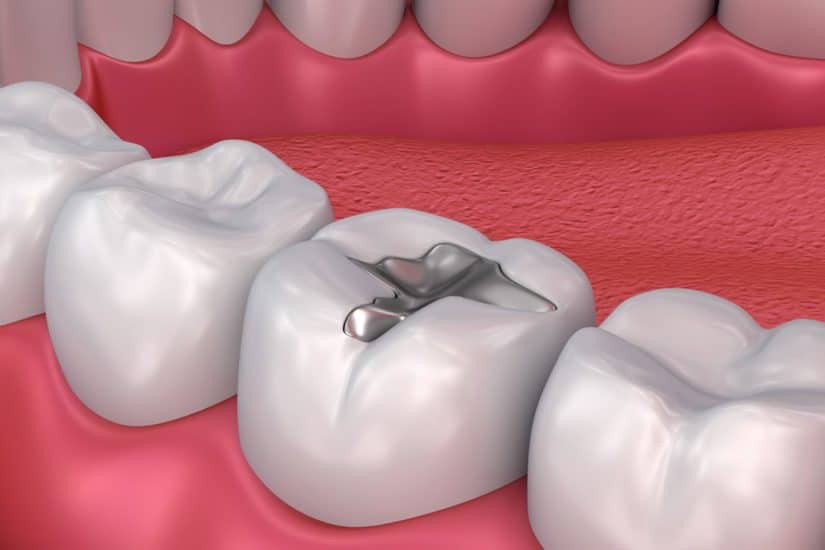

حشوات فضية

المزايا:

- المتانة تستمر ما لا يقل عن 10 إلى 15 سنة وعادةً ما تدوم أكثر من الحشوات المركبة.

- القوة حيث يمكنها تحمل قوى المضغ.

- المصاريف فهي أقل تكلفة من الحشوات المركبة.

السلبيات:

- سوء الجماليات فالحشوات لا تتطابق مع لون الأسنان الطبيعية.

- تدمير المزيد من بنية الأسنان حيث يجب أحياناً إزالة الأجزاء السليمة من الأسنان لتوفير مساحة كبيرة بما يكفي لاحتواء حشوة الملغم.

- تغير اللون حيث يمكن أن تخلق حشوات الملغم صبغة رمادية على بنية الأسنان المحيطة بها.

- التشققات والكسور فعلى الرغم من أن جميع الأسنان تتمدد وتتقلص في وجود السوائل الساخنة والباردة والتي يمكن أن تسبب في تشقق أو كسر الأسنان إلا أن مواد الملغم بالمقارنة مع غيرها من مواد التعبئة فقد تشهد درجة أوسع من التوسع ويؤدي الانكماش إلى ارتفاع معدل التشققات والكسور.

- ردود الفعل التحسسية حيث نسبة صغيرة من الناس ما يقرب 1٪ لديهم حساسية من الزئبق الموجود في حشوات الملغم.